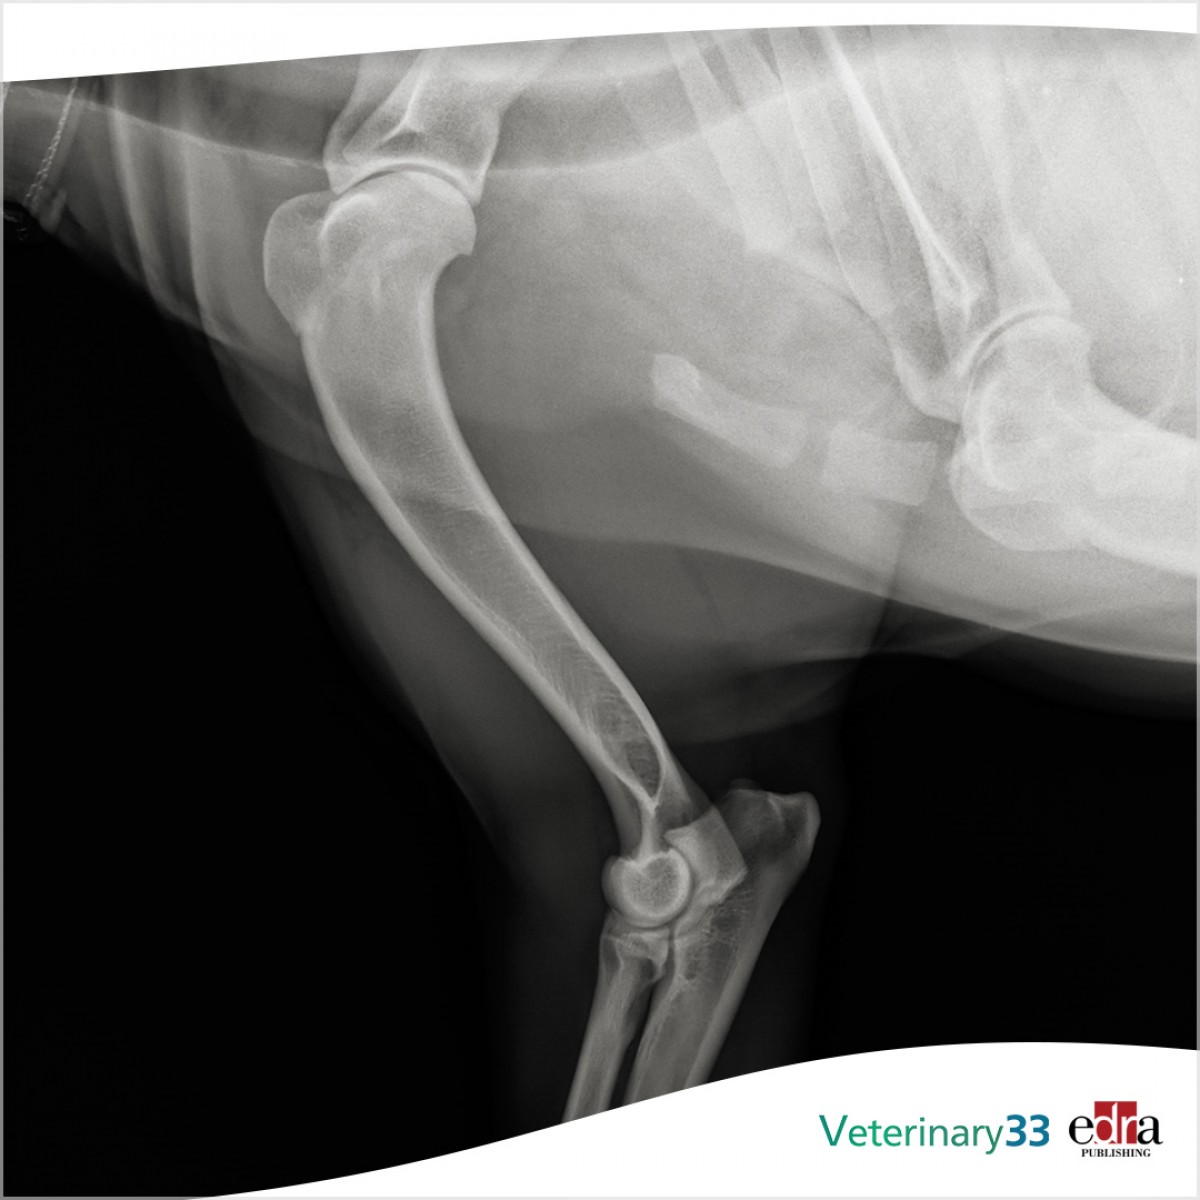

Comparison of Two Stifle Exploratory Methods Using Mini-Arthrotomy for Diagnosis of Canine Medial Meniscal Pathology: An Ex Vivo Study

Objective: The main aim of this study was to compare the accuracy of stifle exploratory using either a stifle distractor (SD method) or a combination of Hohmann and Senn retractors (HS method) for diagnosing canine medial meniscal tears in cranial cruciate ligament-deficient stifles.

Study design: Fifteen pairs of canine cadaveric pelvic limbs were used and cranial cruciate ligaments were transected in all stifles. Paired limbs were then randomly assigned to one of five groups based on the tears created in the caudal pole of the medial meniscus: no tear, peripheral detachment, or a variation in three vertical longitudinal tears. A craniomedial mini-arthrotomy was performed by two observers and a diagnosis of the medial meniscal status was made utilizing the HS and SD methods. Correct diagnosis of the meniscal tear was compared for both methods and observers.

Results: Correct diagnoses were made using the HS and SD methods in 24/30 and 24/30 cases for observer 1 respectively, and in 17/30 and 19/30 cases for observer 2 respectively. There was no significant difference in the correct diagnosis of meniscal tears within each observer between the two methods.

Conclusion: Both HS and SD methods have equal accuracy for the diagnosis of canine medial meniscal pathology for a board-certified surgeon. Unassisted surgeons using the SD method for the evaluation of the medial meniscus are at no diagnostic disadvantage compared with assisted surgeons utilizing the HS method.